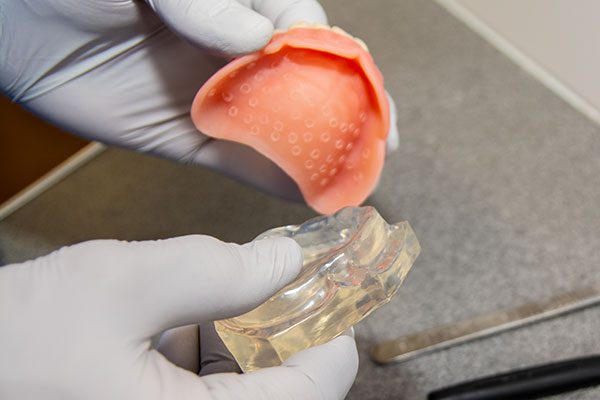

Suction cup dentures effectively “suction” to the mouth to enable a secure fit. We line our suction cups with a layer of silicone material which adheres to the oral tissue without irritating.

This layer contains small bumps known as valves which when pressed into place, trap a small amount of moisture and air. When pressure is relieved, the denture will stay in place. It is the pressure created within the valves that causes the retention of the denture to the mouth.